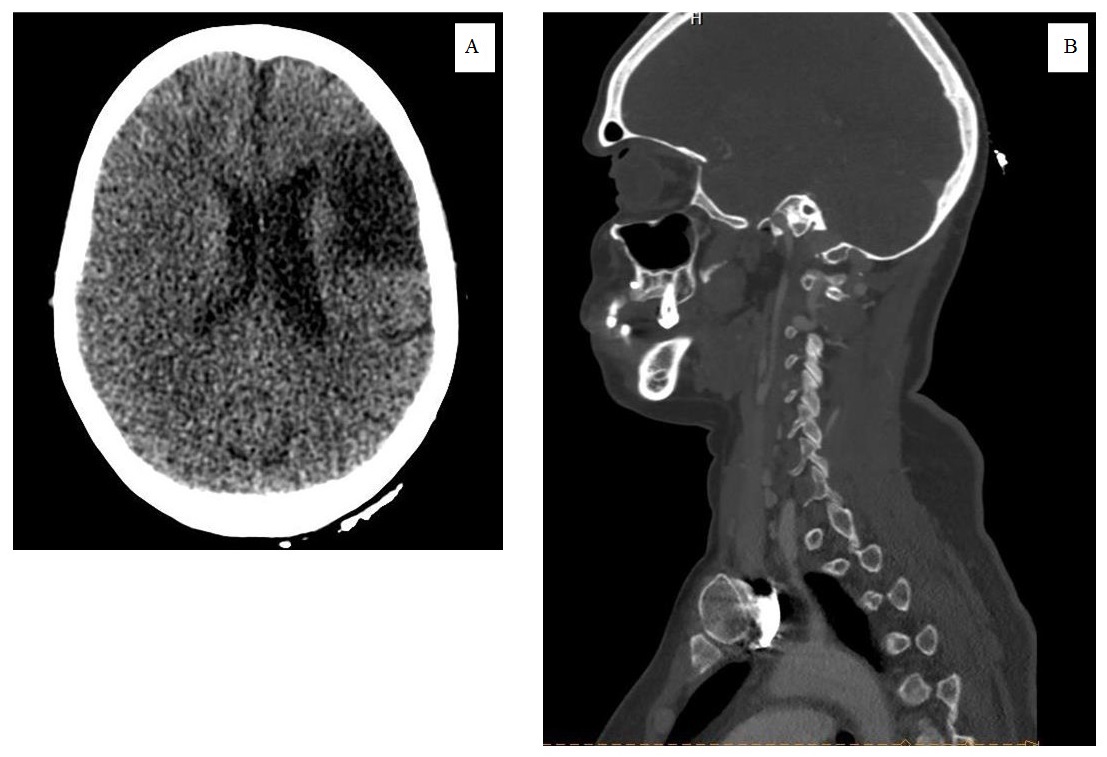

The patient was then transferred to Vishnevsky Scientific Medical Research Center of Surgery to continue the treatment for the vascular pathology, where, on the 5th day after surgery, a control CT of BCA was performed in the angiographic mode. The obtained tomograms permitted to suspect parietal thrombosis in the lumen of the left ICA of up to 14 mm length that narrowed the lumen in the zone of anastomose to 80% (Figure 5).

Fig. 5. Computed tomography of brachiocephalic arteries in the angiographic mode after transfer from a gynecological hospital: alterations in the zone of bifurcation of the carotid artery interpreted as parietal thrombosis (the zone of the expected thrombosis is isolated).